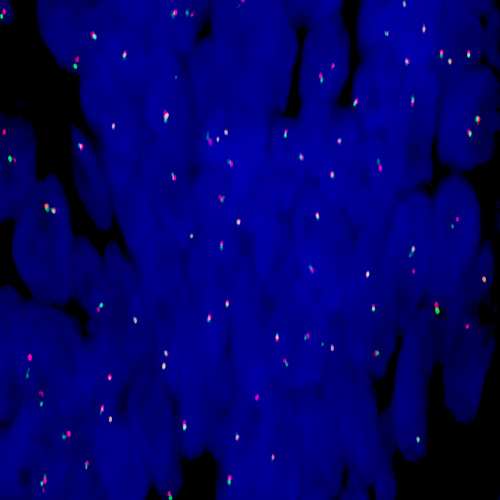

Adenocarcinoma of the lung stained using Kreatech ALK (2p23) Break

XL probe for BOND (KBI-XL001).

ALK (2p23) Break - XL for BOND FISH probe detects genomic translocations involving the ALK gene. ALK (2p23) Proximal - XL and ALK (2p23) Distal - XL probes are optimized to detect the genomic regions proximal and distal to break points in the ALK gene region.

When combined, both probes are used to detect translocations involving the ALK gene at 2p23.